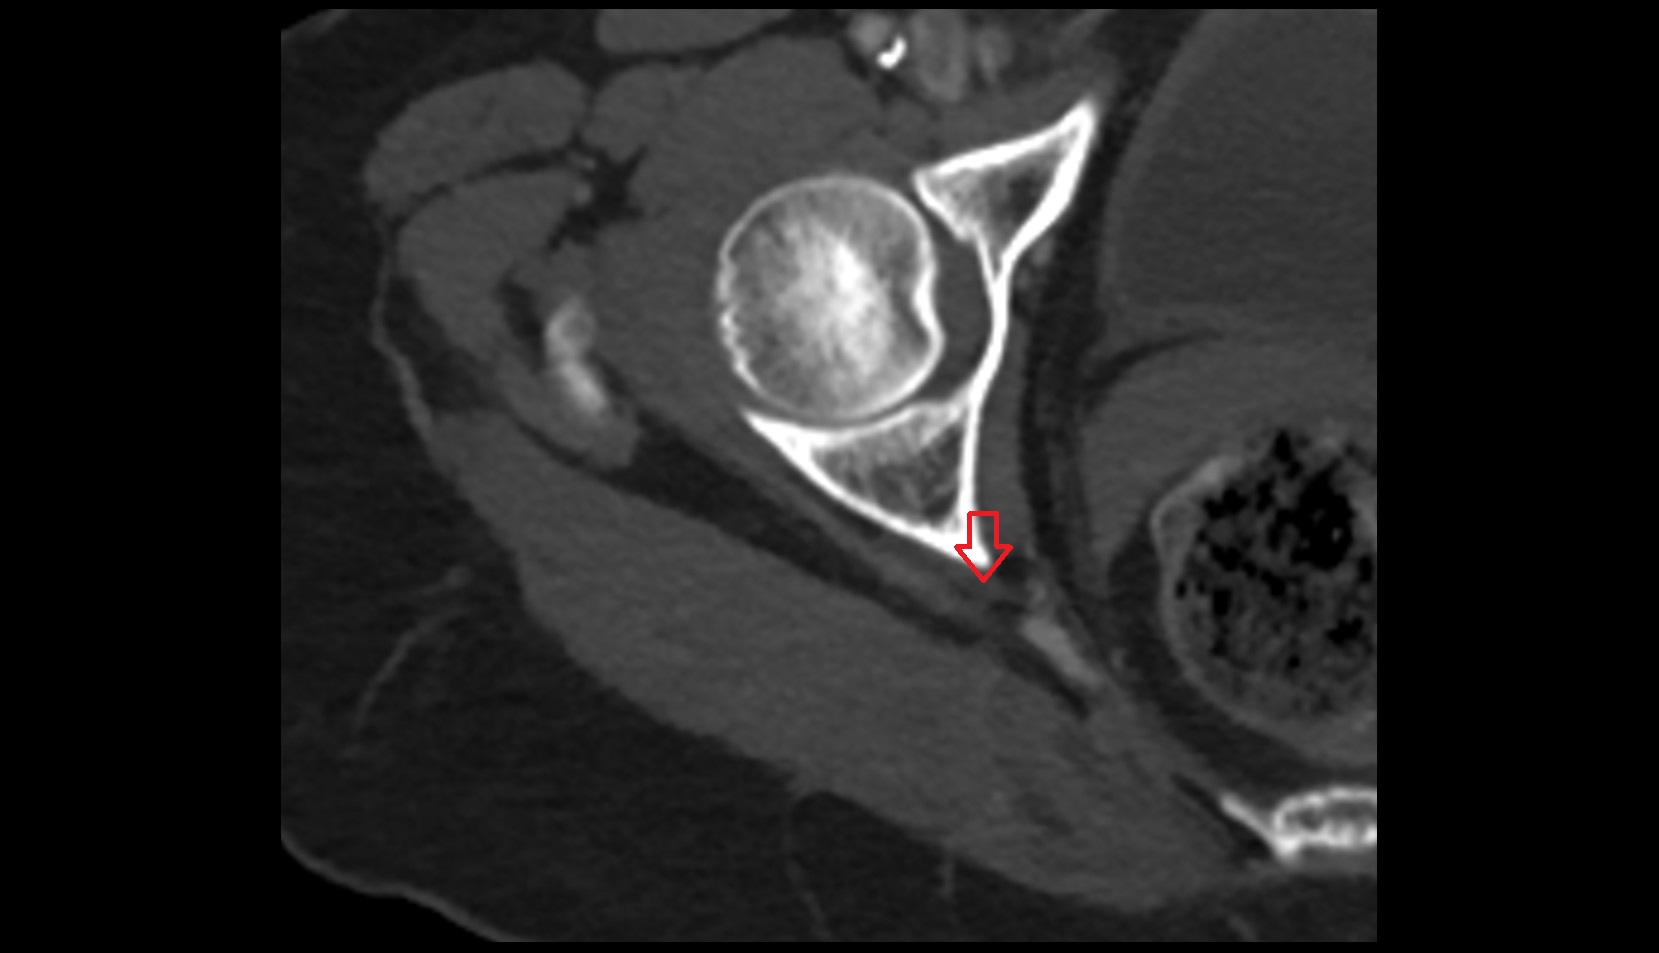

- Articular capsule of hip joint